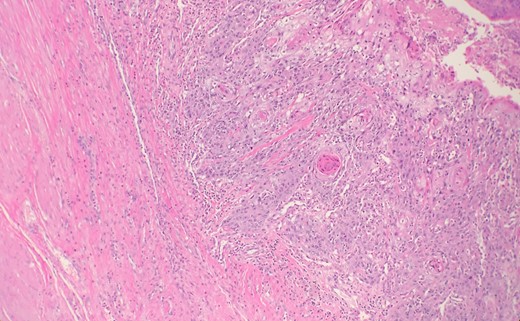

The histopathology of the bladder revealed stage IIIA (T3b) invasive and poorly differentiated urothelial cell carcinoma (Fig. 1) with areas of mullerian and squamous cell carcinoma features (Fig. 2). Histology also showed areas of necrosis and acute inflammatory changes.

Microscopic examination reveals some areas show squamous differentiation with keratin pearls.